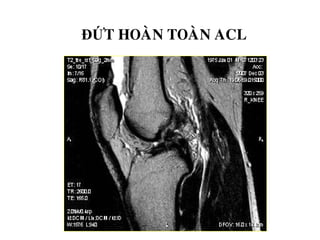

TOÅN THÖÔNG DAÂY CHAÈNG CHEÙO

- Daây chaèng coù höôùng ñi baát thöôøng, maát lieân tuïc moät

phaàn, coù tín hieäu dòch cao treân T2W beân trong, daây

chaèng phuø daøy leân (toån thöông caáp) hay khoâng daøy (toån

thöông maïn).

- Maát lieân tuïc hoaøn toaøn, khoâng thaáy daây chaèng treân

phim.

ĐỨT HOAØN TOAØN ACL